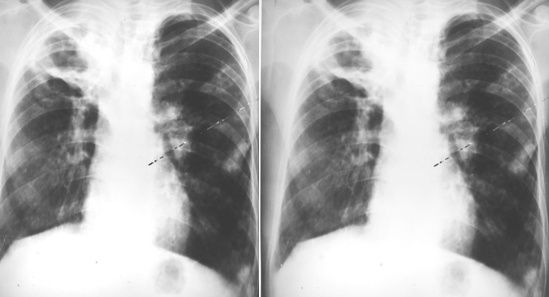

右上肺结核性空洞伴两肺播散

图片

胸部正位片示:右上肺见大片状密度增高影,边缘模糊,内见空洞影,两见两肺沿气道分布的片状、结节状播散灶